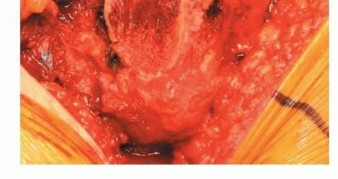

1. كشف الحُق

الشكل التوضيحي 1: كشف الحُق. أ. وضعية الاستلقاء للمدخل الجانبي المعدل. ب. كشف الحُق بالكامل. الجدار الإنسي والتشريح الحُقّي الأصلي مرئيان بسهولة. ج. تتم إزالة الشفة الحُقّية. د. يقوم المشرط العظمي بإزالة النتوءات العظمية من الحفرة الكوتيلويدية. هـ. تزيل المكشطة الأنسجة المتبقية لكشف علامة الدمعة.

توضع المباعدات في المواضع الأمامية، العلوية، والسفلية، مما يكشف محيط الحُق بالكامل. تتم إزالة الشفة الحُقّية. تتم إزالة الأنسجة الرخوة في الحفرة الكوتيلويدية، مما يسمح بكشف الجدار الإنسي وعلامة الدمعة.